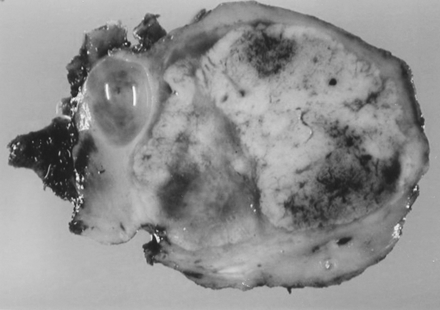

SPLENECTOMIA - CHIRURGIE

SPLENECTOMIA - CHIRURGIE I. DEFINITIE Splenectomia este interventia prin care se realizeaza extirparea splinei. II. ISTORIC Vesalius (1514-1564) a efectuat splenectomii la animale demonstrand ca splina nu este un organ vital. PrimaCiteste tot ... 2644 cuvinte